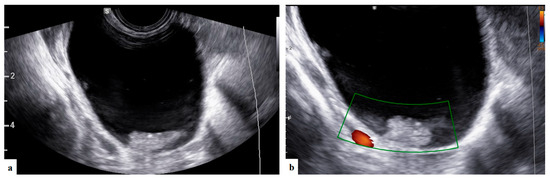

- Bruno, M.; Capanna, G.; Di Florio, C.; Sollima, L.; Guido, M.; Ludovisi, M. Sonographic characteristics of ovarian Leydig cell tumor. Ultrasound Obstet Gynecol. 2023, 62, 441–442. [Google Scholar] [CrossRef]

| Papillation flow Present Absent | 2/4 2/4 |

| Height of the largest papillary projection (mm) (range) | 7.5 (3–13) |